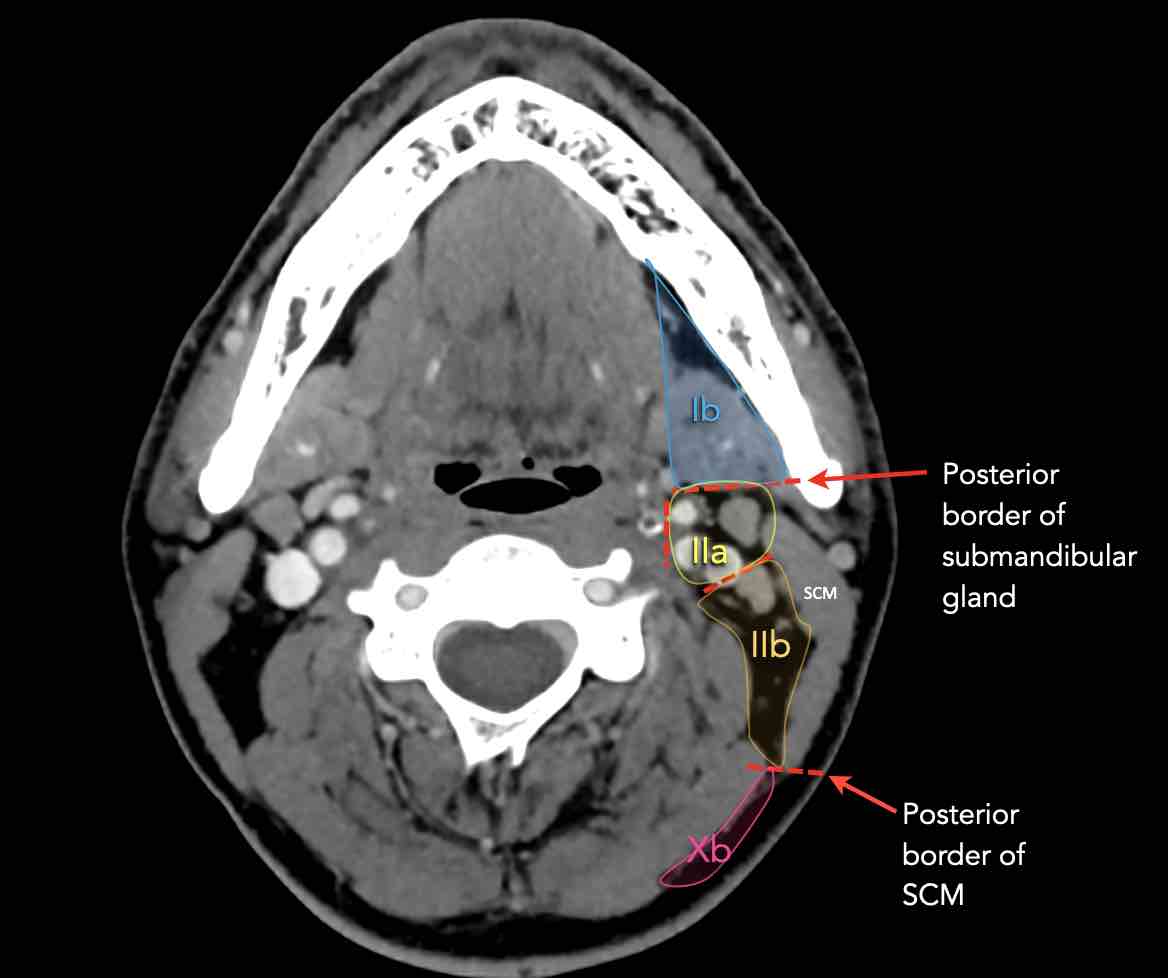

Tầng Ib

chứa các hạch dưới hàm nằm trong khoang giữa mặt trong của xương hàm dưới ở phía ngoài và cơ nhị thân ở phía trong, từ khớp mu cằm ở phía trước đến tuyến dưới hàm ở phía sau.

Tầng II có thể được chia thành tầng IIa và tầng IIb bằng cách vẽ một đường tại bờ sau của tĩnh mạch cảnh trong.

Các hạch bạch huyết ở tầng IIa và IIb có nguy cơ chứa di căn từ các ung thư hốc mũi và khoang miệng, vòm hầu, hầu miệng, hạ hầu, thanh quản và các tuyến nước bọt lớn.